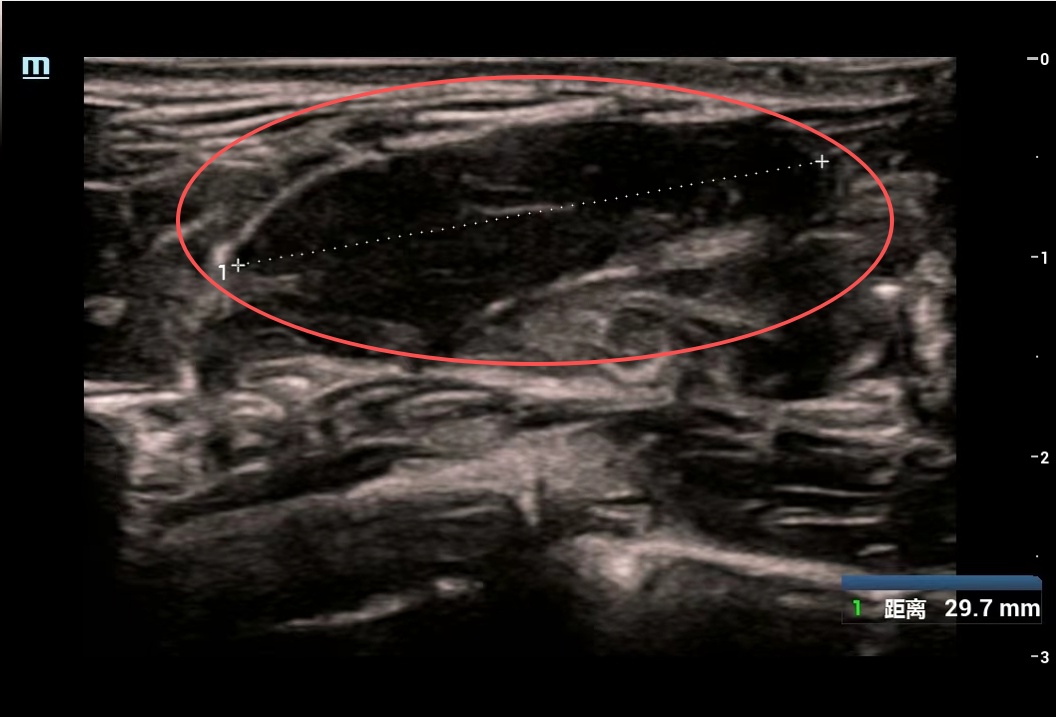

美美的检查结果让医生与家属心头一紧:她的双侧乳房内竟散落84个大小不一的肿块,其中最大一个达6厘米×5厘米,如同鹅蛋大小。

▲ 美美的影像检查部分截图,画圈位置为较大肿块

虽然彩超乳腺分级标准为3级,穿刺活检显示为良性结节,但如此庞大的数量和体积的肿块,已严重威胁乳腺健康,需手术处理。